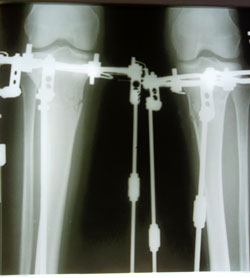

- Диагноз: О-образная деформация нижних конечностей

Всем привет! Прежде хочу поздравить С Праздником! Любви и Счастья!Sekretar Onipko писал(а):15 дней после операции.

Всем добрый вечер!Sekretar Onipko писал(а):Ножки на сегодня.

Сегодня мой 19 день после операции. Крутки почти закончились. Завтра рентген и на фиксацию. Ужасно хочется домой,по деткам соскучилась. Как говорится здесь хорошо, но дома лучше. Если все нормально будет в пятницу домой-домой-домой.

.... преображение отличное... но обрати внимание на правую ножку... посоветуйся с НН еще раз...

Приветики! Сегодня мой 23 день после ОП, чем ближе к фиксации тем больше сомнений... Ляля, спасибо тебе за совет, завтра когда НН на фиксацию придет обязательно посоветуюсь, и домоййййй!